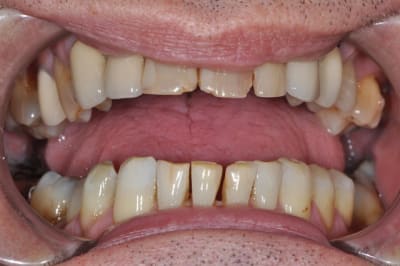

ce patient a une demande essentiellement esthétique,

que me conseilleriez-vous au niveau

des incisives supérieures ?

11 et 21 sont vitales.

effectivement pour le bas traitement à minima,

éclaircissement en cours puis réalisation de composites proximaux,

pour le haut je ne suis pas sur que la forme de la 12 soit très esthétique,

ainsi est-ce que refaire la 12 et cc pour 22 21 11 parait pertinent ?

sauf que si on refait 12 en gardant l'inlay-core ( je suis toujours prudent avec les déposes !!), cela vaut-il le coup de faire des cc ?

le patient sourit ainsi,

il est complexé par ses dents de devant depuis de nombreuses années ( il a 58 ans )

son souhait n'est pas d'avoir la bouche parfaite mais de pouvoir sourire.